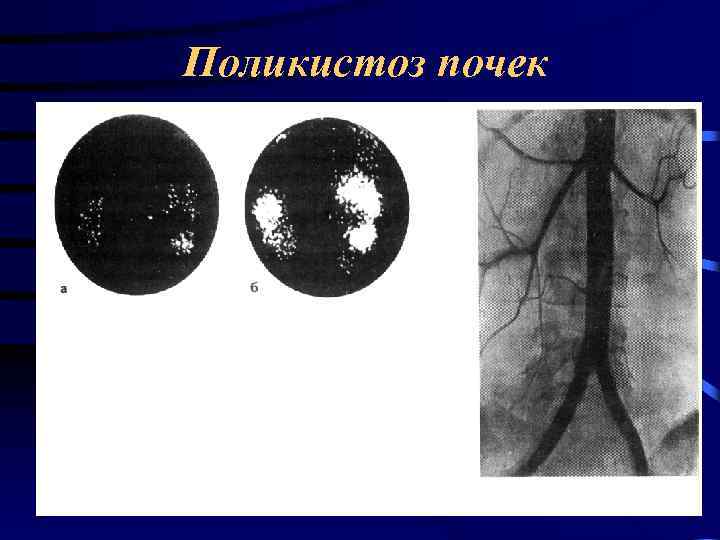

Поликистоз почек

Поликистоз почек

Поликистоз почек

Поликистоз почек

Поликистоз почек

Поликистоз почек